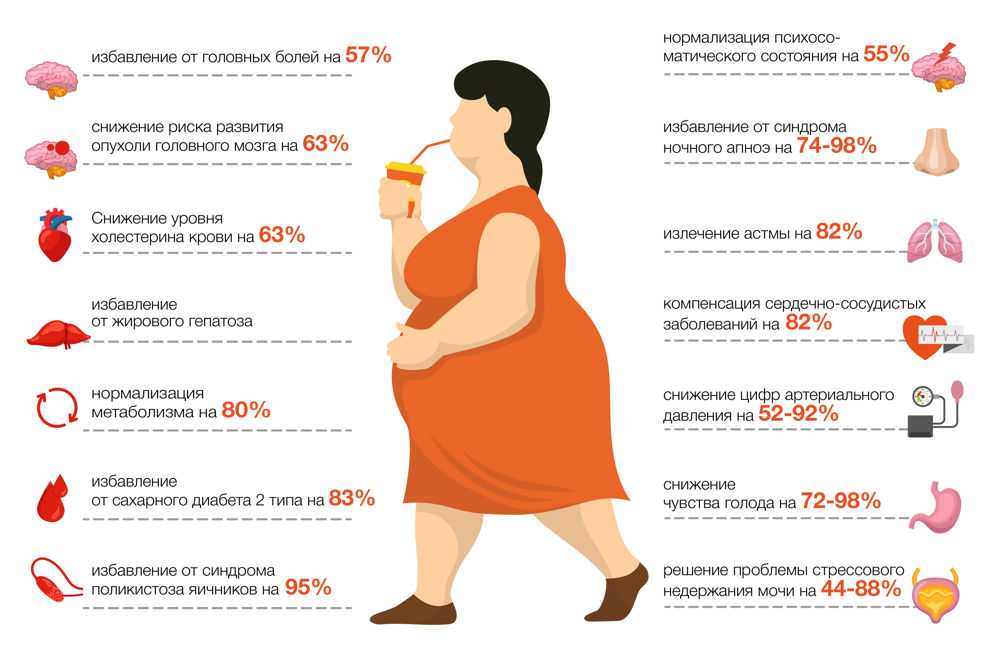

Практические советы по лечению ожирения печени в домашних условиях

Узнайте, как можно эффективно и безопасно лечить ожирение печени в домашних условиях с помощью простых рекомендаций и советов. Избавьтесь от этого заболевания и улучшите свое здоровье с легкостью.